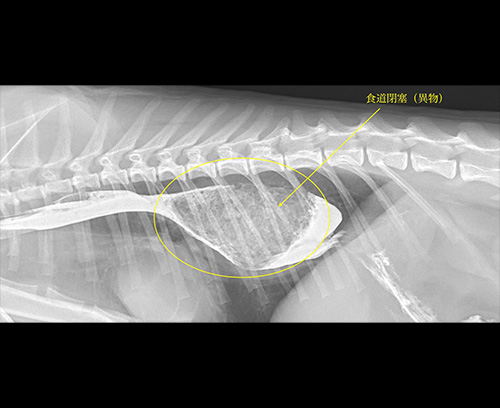

食道異物

食道異物による閉塞(おやつ)